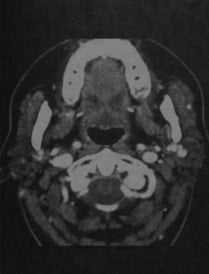

Синдром Шегрена. КТ с контрасти рованием: неоднородная плотность паренхимы обеих желез и уменьшение их размеров вследствие фиброза.